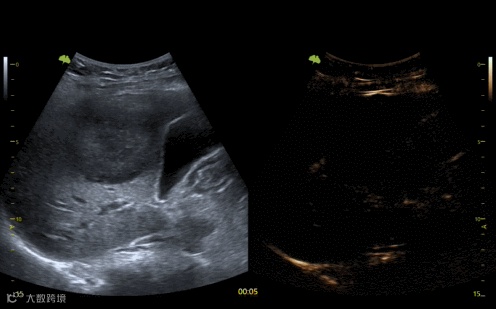

URM超分辨显微成像技术

被业内专家评价为

“未来10年内超声行业

最重要的一次技术突破”

“URM超分辨显微成像技术就相当于把血管放在显微镜下看,即使是三四毫米大小的肿块也能清晰地观察到它的血供情况。”飞依诺联合创始人田园介绍说。

这是一项基础性技术突破,可以广泛应用于肿瘤良恶性判断、治疗效果评估、器官移植评估等方面,只要是有血管、有微循环的地方,都可以通过这项技术去观测它的变化,据此改变临床的治疗路径,实现精准医疗。